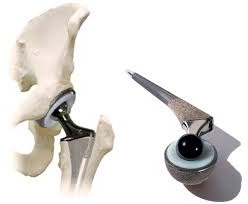

Тотальное эндопротезирование тазобедренного сустава – это операция, когда выполняют удаление поврежденной кости и хряща, с последующей заменой на протез, как головки бедренной кости, так и вертлужной впадины.

Протезы с «бесцементным» типом фиксации покрыты специальным пористым материалом, который позволяет костной ткани пациента по прошествии определенного времени врастать в эти микроскопические поры. Во время операции компоненты эндопротеза – вертлужный компонент (чашка) и бедренный компонент (ножка) впрессовываются в кость для первичной фиксации протеза. Далее, через определенный промежуток времени, костные клетки проникают в специальное пористое покрытие компонентов эндопротеза (кость — это тоже живая ткань), что обеспечивает отличную фиксацию эндопротеза в кости пациента без применения каких-либо дополнительных материалов (без костного цемента).